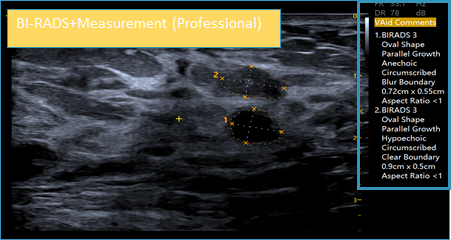

- VAid Breast: KI-gestützte automatische Detektion und Vermessung von Läsionen in der Brust